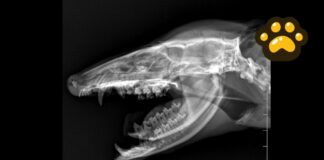

Tlacuache atropellado en Puebla recibe atención; su estado de salud es...

Personal médico veterinario del área de vida silvestre de la Secretaría de Medio Ambiente de Puebla brindó atención a un tlacuache macho de 1.7...